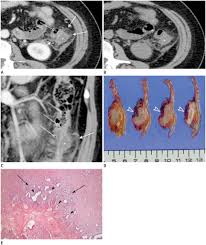

Fdg Pet Value In Deep Endometriosis Gynecological Surgery Full Text from media.springernature.com This type of endometriosis is called, deeply infiltrating or deeply infiltrative endometriosis die because it is found deep within the tissue or organ. It may vary from microscopic endometriotic implants to large cysts (endometriomas). After taking your medical and symptom history, and after performing a pelvic exam, your provider may recommend imaging. Although the ovary is the most common site of involvement, endometriotic implants may occur in other locations outside the pelvis. Endometriosis is a painful condition in which tissue that normally lines your uterus (endometrial tissue) grows in other parts of your pelvis, such as your ovaries or fallopian tubes. Endometriosis is a condition in which the type of tissue that forms the lining of the uterus (the endometrium) is found outside the uterus. Learn about treatment, causes, stages, surgery, and diagnosis. An ultrasound, a ct scan, or an mri can make detailed pictures of your organs.

Although the ovary is the most common site of involvement, endometriotic implants may occur in other locations outside the pelvis.

The most common symptom is pelvic pain. Plain film radiography, computed tomography (ct) scanning, and barium studies are not sensitive for the diagnosis of endometriosis. This type of endometriosis is called, deeply infiltrating or deeply infiltrative endometriosis die because it is found deep within the tissue or organ. Endometriosis is an important cause of chronic pelvic pain and infertility. The most common symptom of thoracic endometriosis is chest pain occurring right before or during menstruation. To diagnose endometriosis in the bowel, a physician conducts an examination that includes a vaginal examination, ultrasound, and a ct or mri scan. You may be given contrast liquid to help your abdomen show up better in the pictures. Tell the healthcare provider if you have ever had an allergic reaction to contrast liquid. Endometriosis is derived from the word endometrium, which is the tissue that lines the uterus. Endometriosis is defined as the presence of endometrial glandular and/or stromal cells outside of the uterine cavity. Learn about treatment, causes, stages, surgery, and diagnosis. The ct and mr characteristics of abdominal wall endometriosis are nonspecific, both showing a solid enhancing mass in the abdominal wall. The most common sign of endometriosis is pain in your lower belly that doesn't go away.